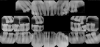

Patient presents with maxillary and mandibular anterior teeth having been extracted and is wearing transitional removable appliances.

Decisions need to be made as to smoking cessation, periodontal treatment and tooth replacement. The photos and dental radiographs were taken prior to the referral (Figure 23 through Figure 25), and the periodontal charting done post-op (Figure 26).

Figure 24.